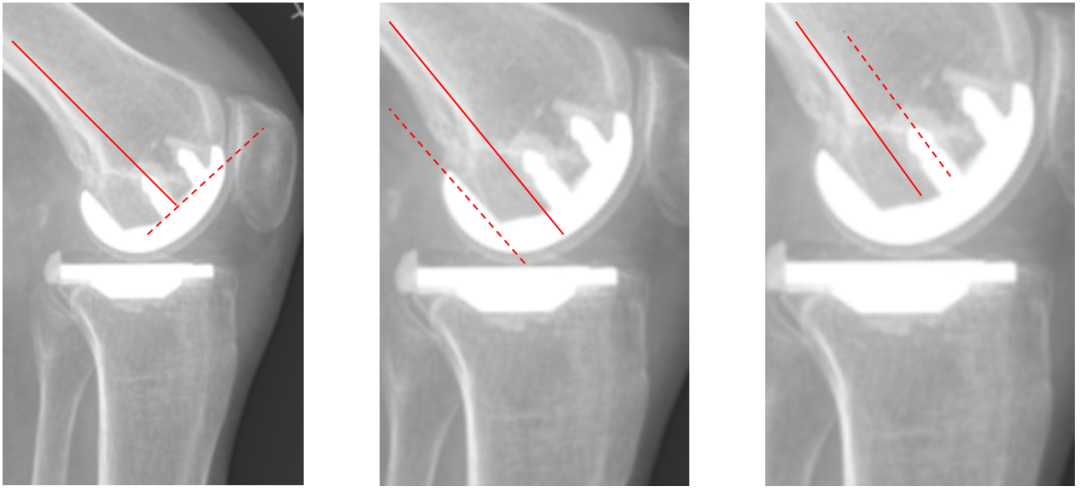

胫骨假体后倾角大

侧位胫骨假体位置:胫骨假体后倾11°,前后缘齐平。

胫骨假体前倾

侧位胫骨假体位置:胫骨假体前倾5°,前后缘齐平。

股骨假体后倾不足

侧位股骨假体位置:股骨假体后倾5°,后髁包容不足。